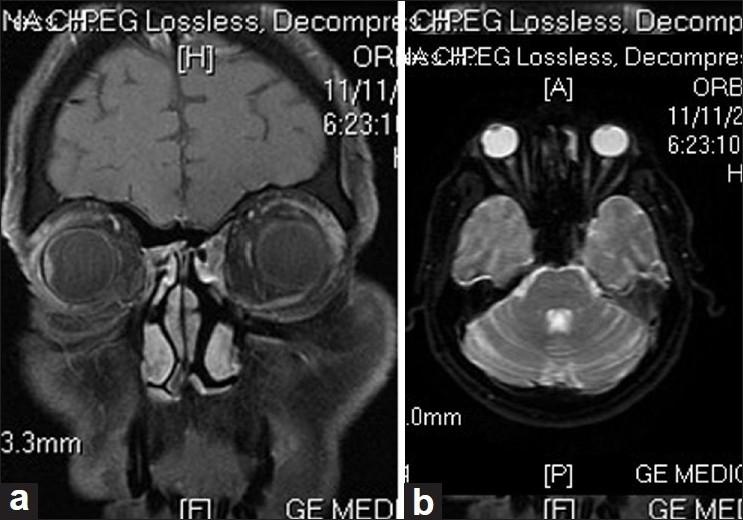

与未经治疗的脉络膜黑色素瘤相关的视网膜下脂质渗出。

Subretinal lipid exudation associated with untreated choroidal melanoma.

Subretinal lipid exudation in an untreated choroidal melanoma is very rare. It is seen following plaque radiotherapy in choroidal melanoma. There is only one case report of untreated choroidal melanoma with massive lipid exudation in a patient with metastatic hypernephroma. We report here a rare case of untreated choroidal melanoma with lipid exudation. Subretinal exudation that is rarely seen following plaque brachytherapy was noted at the borders of this untreated tumor. Lipid exudation partially resolved following brachytherapy.

摘要

未经治疗的脉络膜黑色素瘤很少出现视网膜下脂质渗出。这种情况见于脉络膜黑色素瘤的放射性敷贴治疗后。仅有一例转移性肾细胞瘤患者的未经治疗的脉络膜黑色素瘤伴大量脂质渗出的病例报告。我们在此报告一例罕见的未经治疗的脉络膜黑色素瘤伴脂质渗出的病例。在该未经治疗的肿瘤边缘观察到放射性敷贴治疗后罕见的视网膜下渗出。脂质渗出在放射性敷贴治疗后部分缓解。